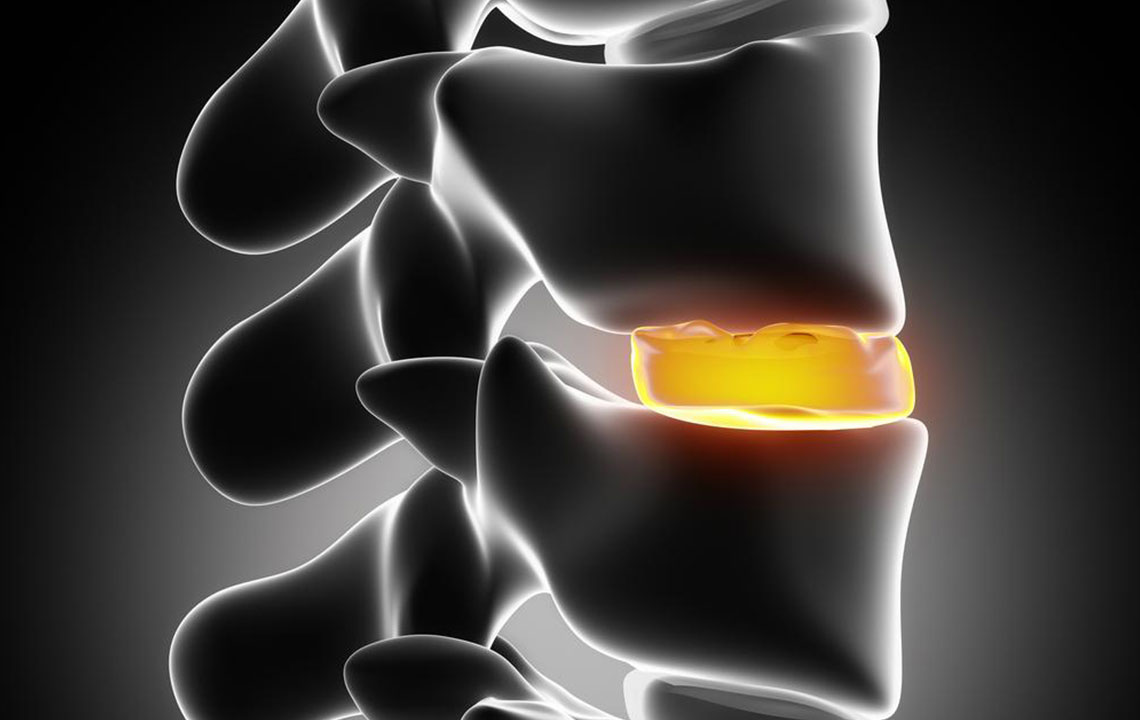

Numbness, muscle weakness or a tingling sensation in one or both your legs are common signs of bulging disc. Bulging disc is a condition where the d isc that is present between you r vertebrae bulges outside the normal space it occupies. It does not cause any rupture, and sometimes it does not even pain much.